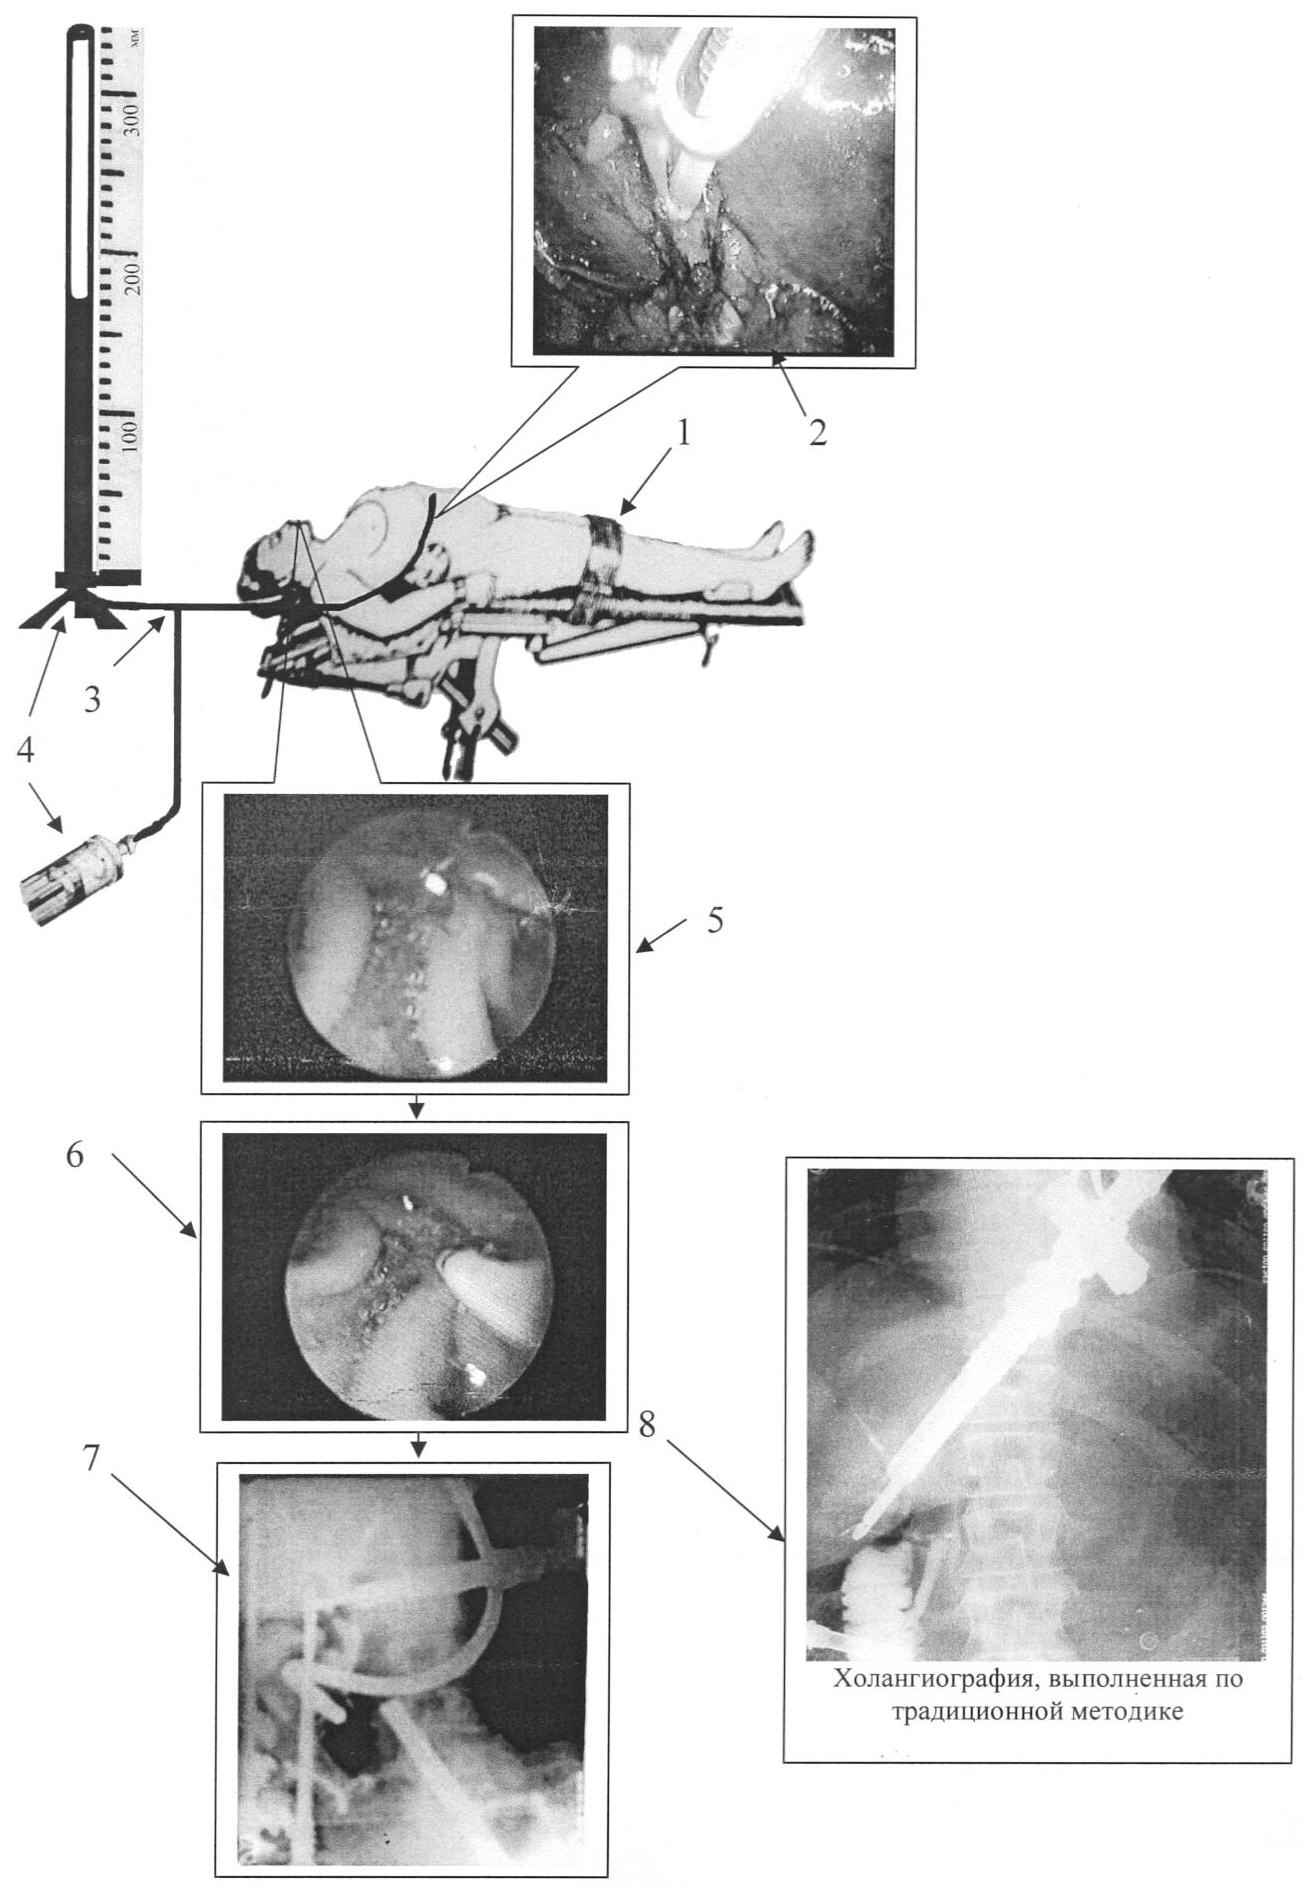

Изобретение поясняется чертежом, на котором изображена схема интраоперационной холангиографии.

Способ осуществляется следующим образом (см. чертеж). Во время выполнения лапароскопической холецистэктомии (1) клипируют пузырный проток ближе к шейке желчного пузыря, после чего просвет вскрывается и катетеризируется при помощи специального катетера (2), который присоединяется при помощи тройника (3) к системе, состоящей из аппарата Вальдмана и шприца для введения растворов (4), затем выполняется дуоденоскопия, во время которой локализуют отверстие БСДК и под его визуальным контролем через катетер вводится 0,5% раствор новокаина, отмечается момент поступления новокаина в двенадцатиперстную кишку, учитывая, что новокаин вызывает терминальную анестезию и расслабление БСДК, по показателям давления на аппарете Вальдмана дифференцируют спазм от стеноза БСДК (5), после этого в желчные протоки вводится контрастное вещество, одновременно дуоденоскопом, либо другим эндоскопическим инструментом перекрывается отверстие БСДК (6). Введение контрастного вещества продолжается до момента достижения давления 250 мм вод. ст., после чего выполняются рентгенограммы (7), на которых видно хорошее контрастирование желчного дерева, в то время как на холангиограммах, выполненных по традиционной методике, контрастируется только дистальный отдел холедоха (8).